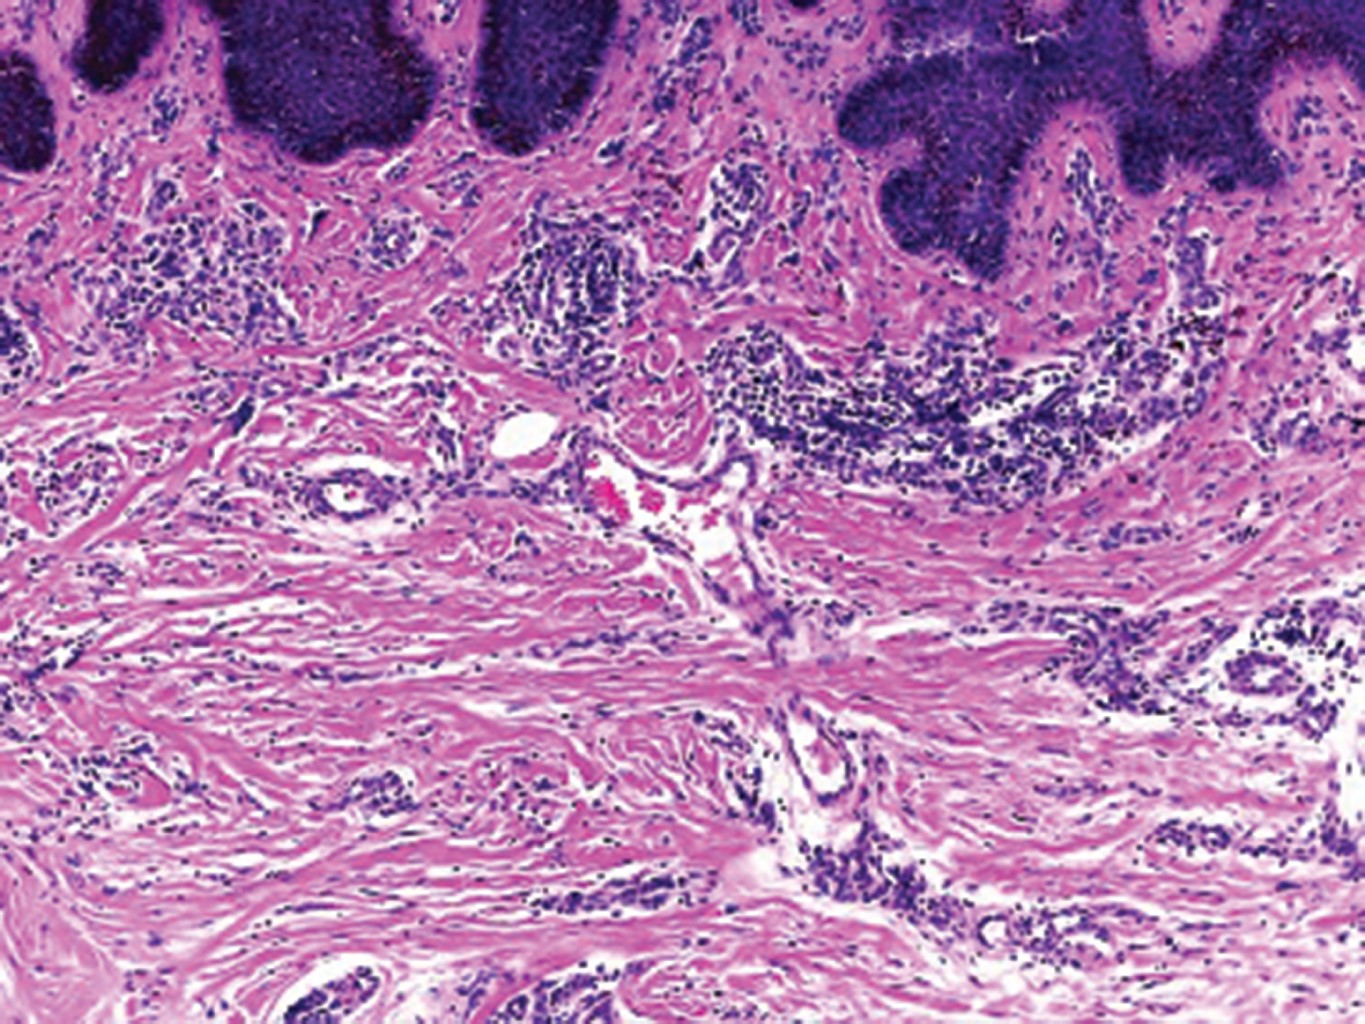

El estudio histológico es diagnóstico con los siguientes hallazgos: proliferación de vasos capilares y vénulas en la dermis superficial y media, cuyo endotelio es prominente y en ocasiones protruye hacia la luz, células multinucleadas que presentan citoplasma angulado con núcleos hipercromáticos en número variable, inmersas en un estroma fibroso.10,11 En la inmunohistoquímica, como es esperado, las células endoteliales expresan factor VIII, CD31 y CD34, mientras que los macrófagos, histiocitos y células multinucleadas expresan factor XIIIa, CD68 (variable) y vimentina.5 La dermatoscopía hasta el momento es inespecífica.12

Al interrogatorio, refiere haber iniciado hace cuatro años con "lunares" de forma lenta y progresiva. Sin tratamiento previo ni antecedentes médicos de relevancia. Clínicamente se hizo el diagnóstico de sarcoma de Kaposi vs histiocitosis y se solicitaron estudios paraclínicos, que descartaron infección por VIH u otras alteraciones. El estudio histológico mostró epidermis normal y en la dermis superficial y media presencia de vasos dilatados, fibrosis y células multinucleadas basofílicas con bordes angulosos (Figuras 3, 4 y 5).